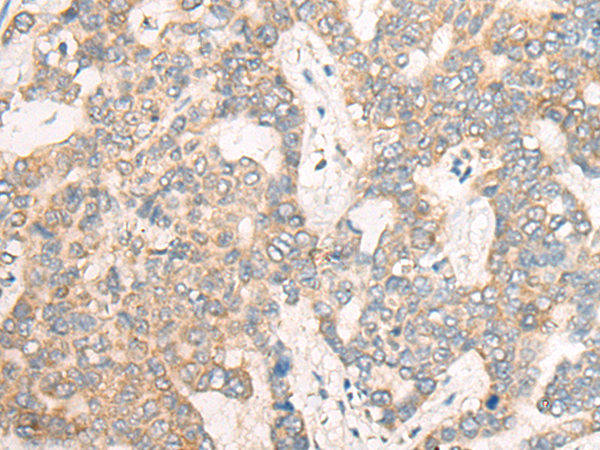

分类: 科研抗体货号: P13166别名: TIM3; CD366; KIM-3; TIMD3; Tim-3; TIMD-3; HAVcr-2应用: IHC反应种属: Human